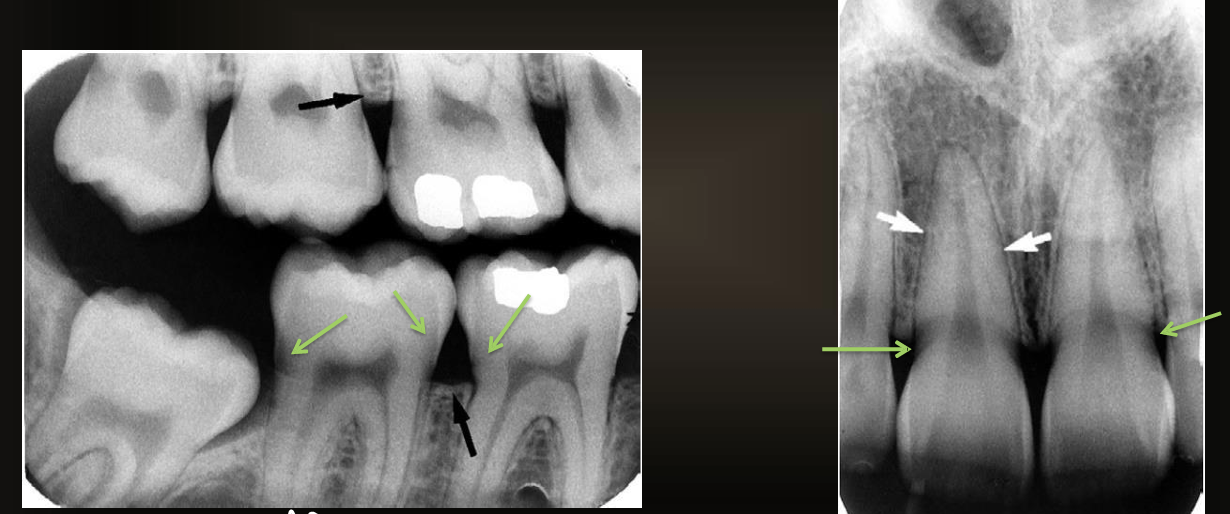

are these caries or restorations with radiolucent material?

caries

are these caries or restorations with radiolucent materials?

restorations with radiolucent materials

what is this arrow pointing at?

secondary caries

what are the green arrows pointing at?

cervical burnout

how can you tell if its cervical burnout or caries?

there is no bone loss, it affects multiple teeth, and if the angle of the radiograph changes the radiolucency is gone